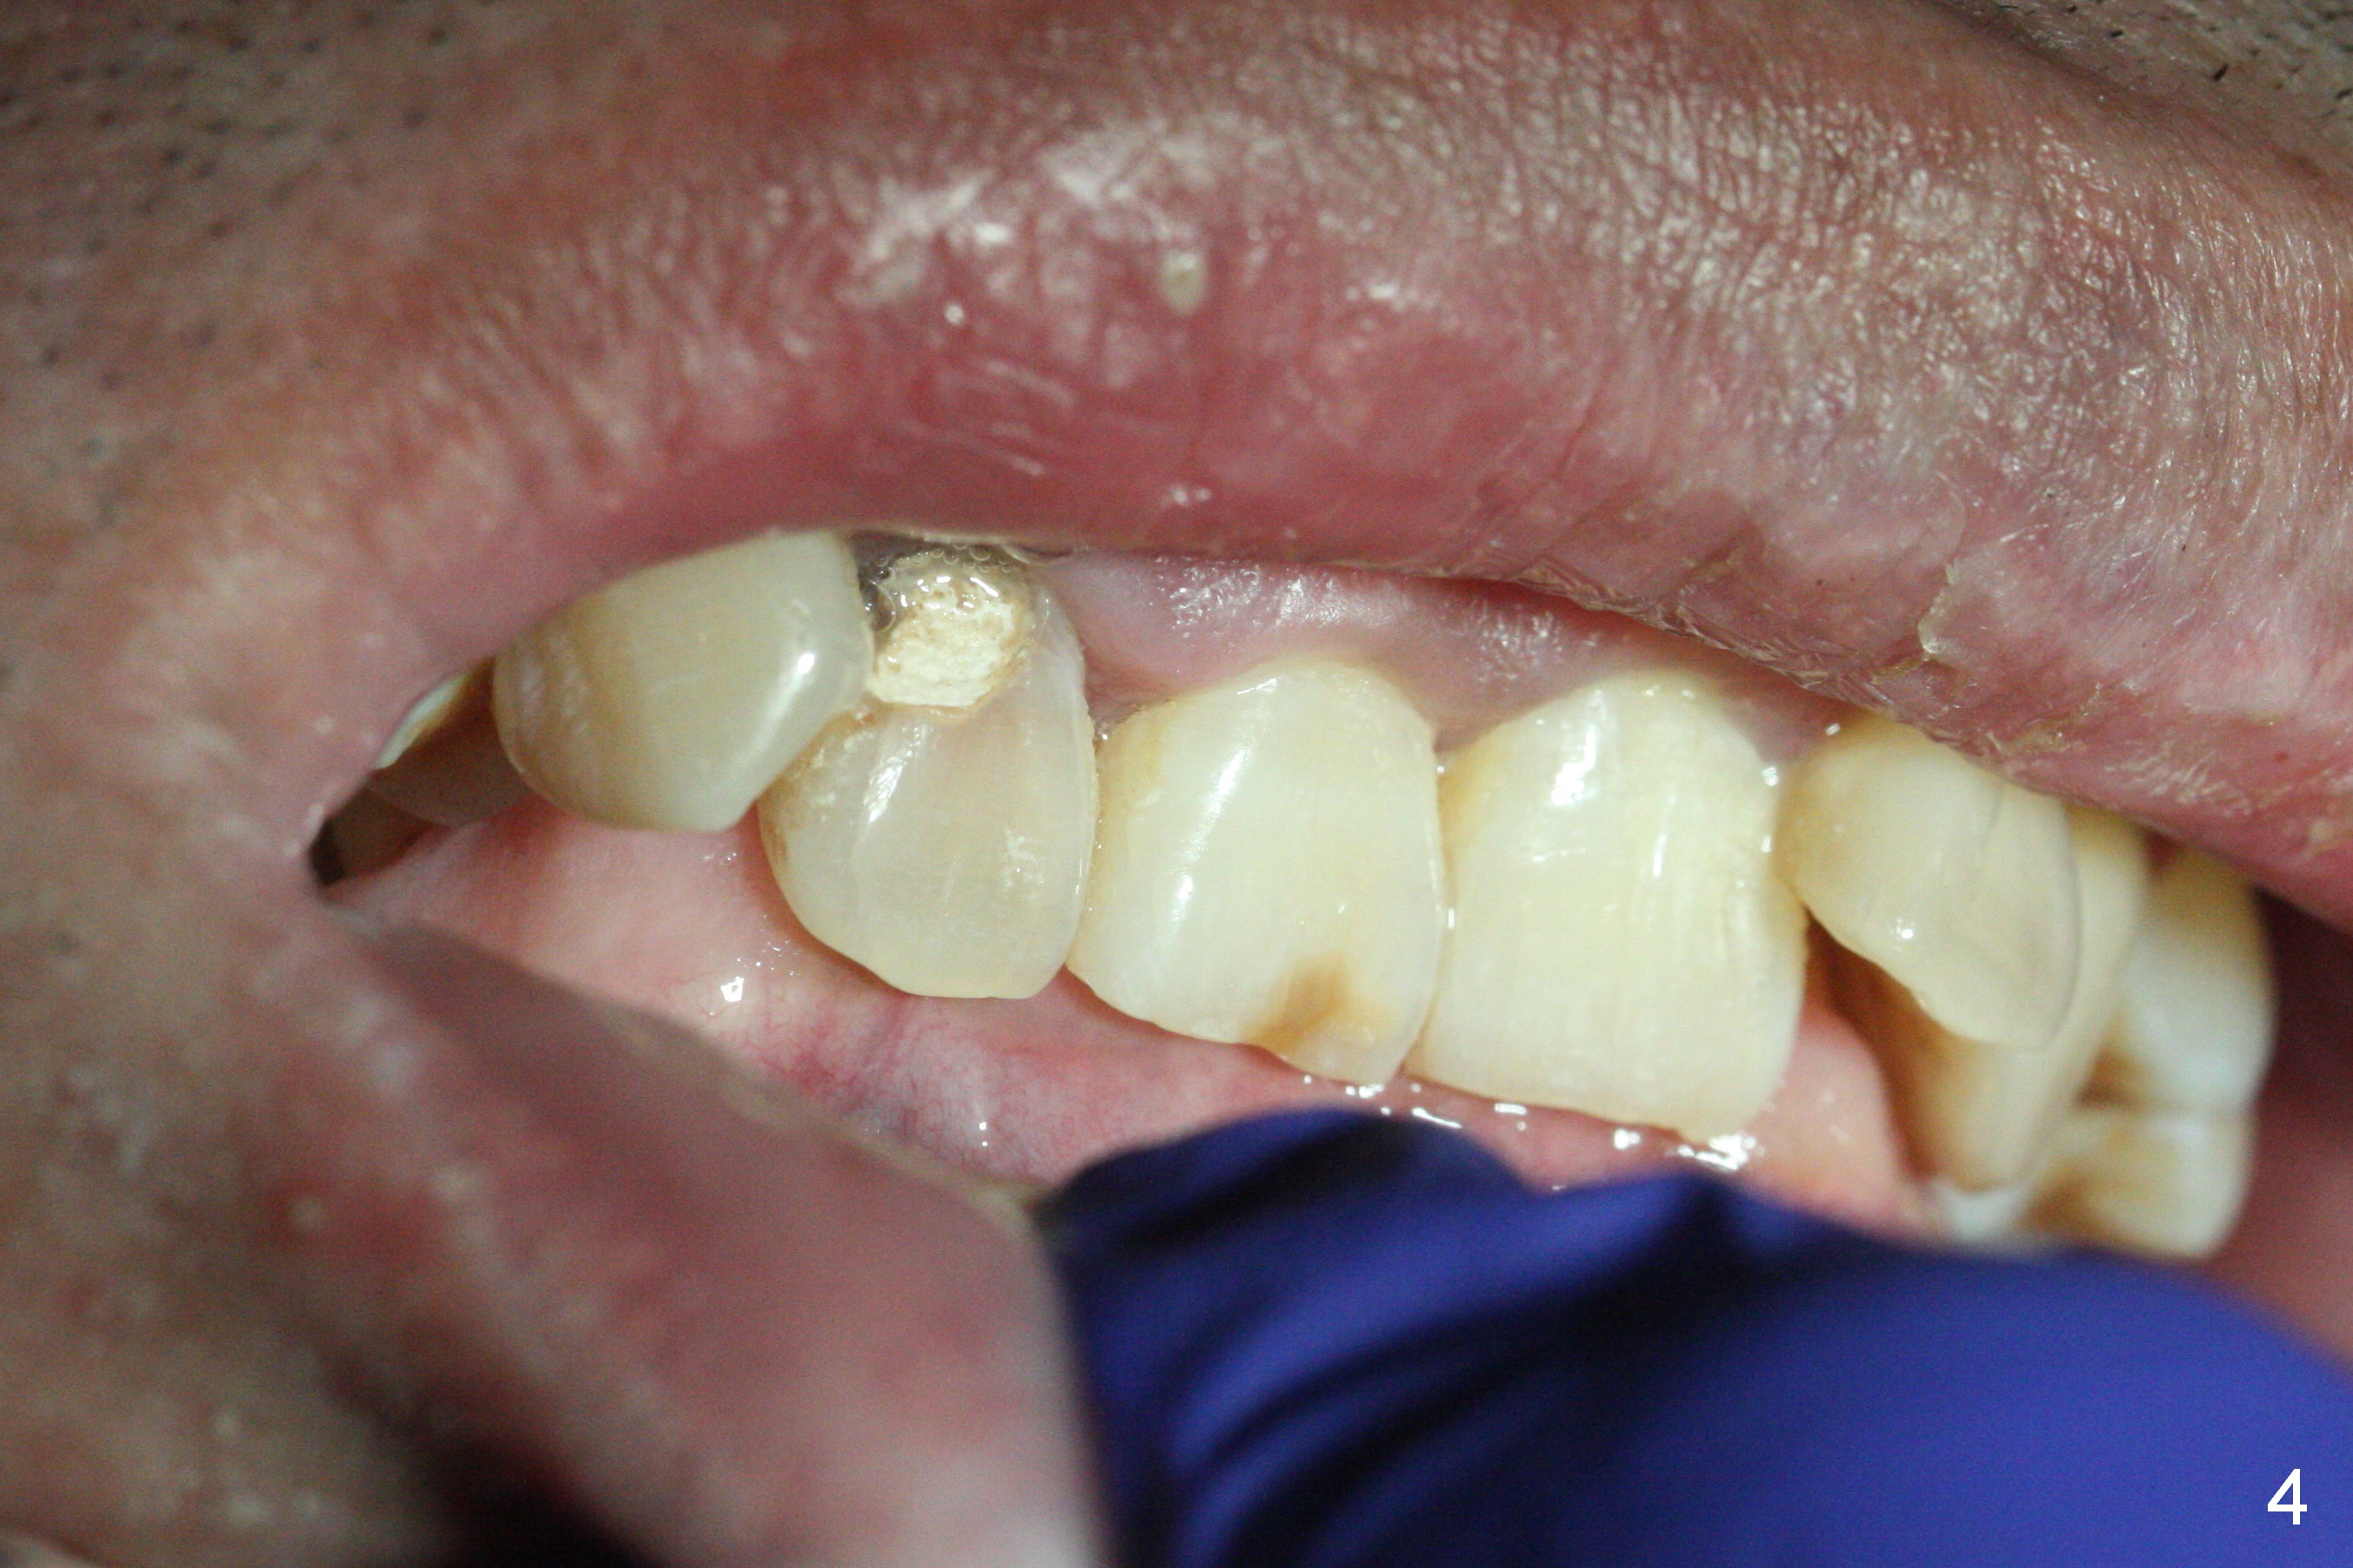

A 52-year-old man had a non-restorable lateral incisor 3 years ago (Fig.1). It fractures lately (Fig.2) with a buccal abscess (Fig.3 *) ) and fistula (>, possible severe buccal plate defect, prepare PRF). Severe deep bite (Fig.4) and malocclusion (Fig.5) will present a challenge to implant provisional restoration.

If the deep bite is a problem, place a healing abutment or the immediate provisional without the palatal apical wall. Or ask the patient in advance whether the right lateral can be placed as labial as the tooth #10 or not (Fig.3-5).